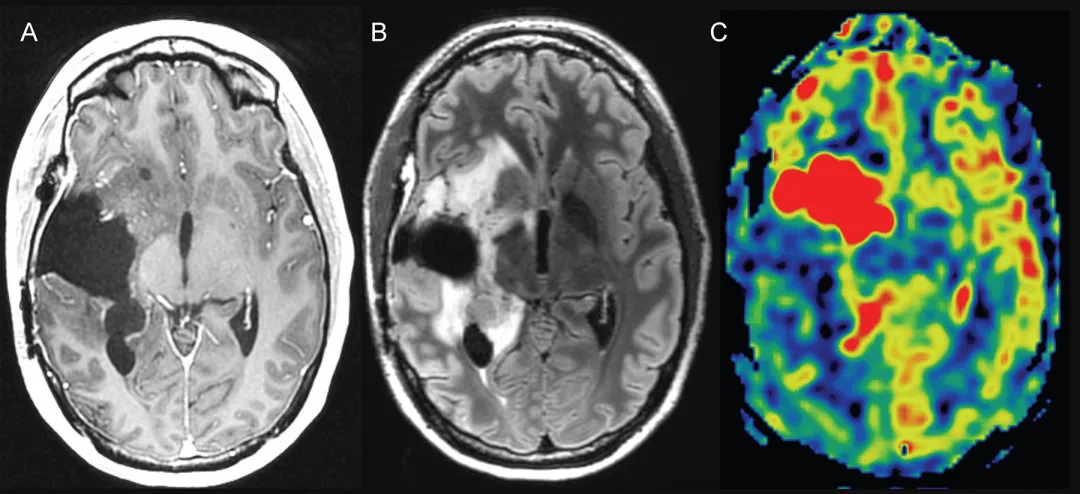

动脉自旋标记成像

动脉自旋标记成像(ASL)可能成为鉴别胶质瘤真性进展与治疗反应的有效替代方法,因其无需使用对比剂且对磁敏感伪影敏感性较低。前瞻性研究报道其诊断能力与动态磁敏感对比成像相当,而动脉自旋标记测得的脑血流量可准确识别IDH突变,显示其独特附加价值。汇总分析表明真性进展组的动脉自旋标记测量脑血流量、相对脑血流量及相对脑血容量均显著更高,报道的平均敏感度与特异度分别为94%与50%。

图3. 动脉自旋标记灌注成像辅助鉴别真性进展

右侧岛叶胶质母细胞瘤放疗后1年

A:轴位T1加权增强MRI显示右侧基底节区切除腔前缘斑点状微弱强化

B:轴位FLAIR图像显示切除腔周围非特异性高信号异常

C:轴位动脉自旋标记灌注图像显示血流量显著增加,针对此区域的再次切除术证实广泛肿瘤复发